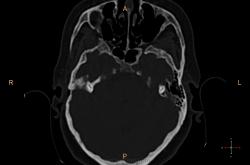

Справа в полости среднего уха небольшое количество жидкости? Пирамида и сосцевидный отросток склерозированы. У нас направляют на КТ только при подозрении на деструкцию или опухоль. Исследование выполняются на специальной программе для височных костей , срезы по 0.1 или 0.05 см, костная структура видна изумительно. А чаще изменения височных костей обнаруживаются как случайная находка при КТ черепа (хорошо видно на "сердечном" режиме).

У нас минимальный срез идет по 0,75мм, мне кажется если есть возможность провести КТ-исследование, следует это делать, что косается данной пациентки, все не так просто, у неё имеется клинически свищ с отделяемым, позади ушной раковины, где имеено и откуда идет свищ четко видно, а так все верно имеется эпитимпанит и антрит.

Согласен, ///если есть возможность провести КТ-исследование, следует это делать///, с Шуллерами-Майерами не сравнить. Кстати, состояние аттико-антральной области обычно более демонстративно на аксиальных срезах уровня латерального полукружного канала.

Касаюсь Андрей Юрьевич, лобарант меня позвал в плане выбора протокола исследования, а я при наложении плоскости сканирование на топограмме, взял и не учел оптико-меатальную линию, получилось несколько неуклюже, поэтому только на станции подорвался выравнивать её при анализе сканов :-(

Свищевой ход.